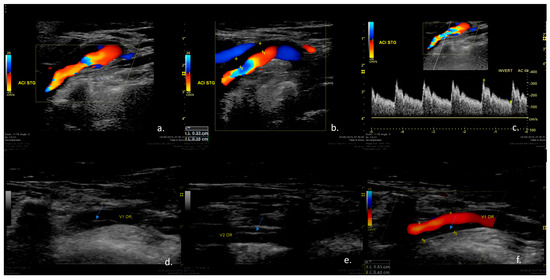

Figure 2. The Case of a 38-year -old marathon runner who presented during a competition a short episode of amaurosis fugax in the left eye and transient speech difficulties associated with cervical pain. Duplex ultrasound examination of the cervical vessels. (a,b) Color-mode examination revealing irregular stenosis at the level of the left ICA caused by hypoechoic vessel wall changes suggestive of mural hematoma. (c) Triplex-mode examination revealing increased blood flow velocities in the left ICA, suggesting severe stenosis. (d,e) B-mode examination of the right vertebral artery showing a hyperechoic line inside the vessel lumen (arrow), suggestive of intimal flap. (f) Color-mode examination of the right vertebral artery showing irregular stenosis caused by a hypoechoic mural hematoma (arrow). Therefore, the patient was diagnosed with two simultaneous cervical artery dissections at the level of the left carotid artery and the level of the right vertebral artery.